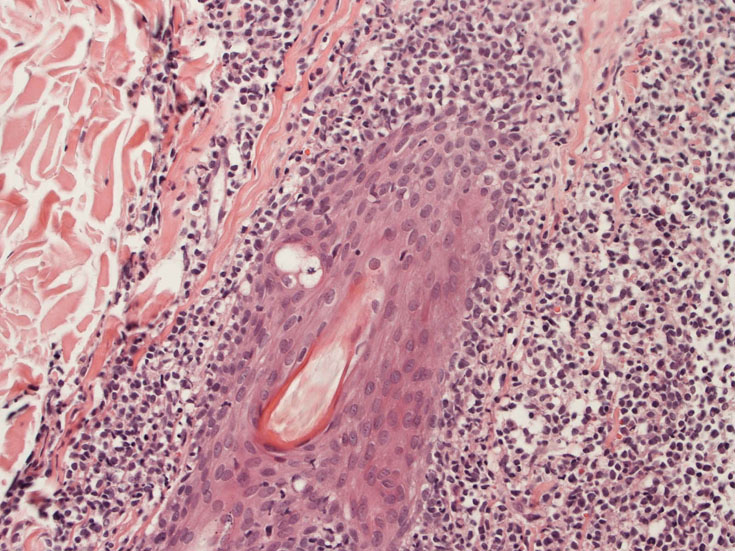

皮膚生検組織病理所見

真皮, 毛嚢周囲, 皮下組織にびまん性または結節様に異型細胞の浸潤増殖が認められる(Fig.05)。表皮への浸潤は認められない。真皮上層への浸潤細胞は類円形,多角形のhyperchromatic nucleiをもつ。細胞質は明るくclearに見える(Fig.06)。毛嚢周囲に浸潤する細胞はリンパ節への浸潤細胞と同様の形態を示す(Fig.7). 腫瘍細胞はCD123陽性を示した(Fig.9)